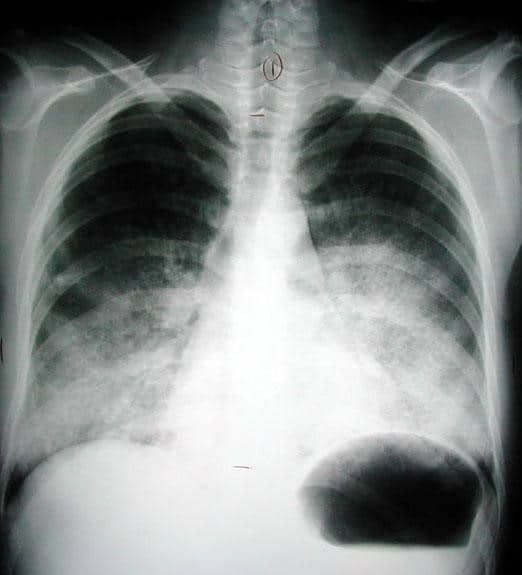

- Lung Injuries: (~15%). “Blast lung” is a major fatal primary injury among initial survivors unique to high-order explosions. This is characterized by clinical triad of apnea, bradycardia, and hypotension. Some of the presenting symptoms include dyspnea, shortness of breath, hemoptysis, or chest pain. A characteristic image finding is shown in figure 1, notably known as the “butterfly” pattern (or Bat wing appearance). Common pulmonary injuries include hemo/pneumothorax, pulmonary contusion, or pulmonary hemorrhage. Overt or occult pneumothoraces is another common injury. We recommend chest tube placement for occult pneumothoraces based on “the 35 mm rule”. Occult pneumothoraces measuring 35 mm or less on the axial CT scan (measuring the radial distance between the parietal/visceral pleura/mediastinum of the largest air pocket) can be safely observed with only 9% failure rate (2).